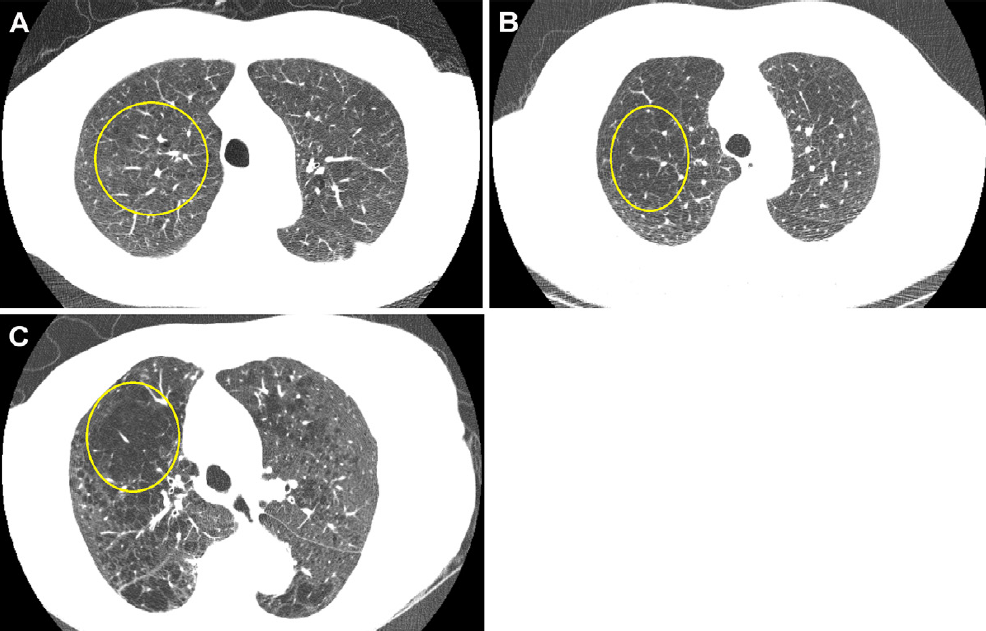

The Landy team sought to identify low-risk individuals in the NLST and estimate how many lung cancers would have been delayed one year in diagnosis had people been assigned to biennial screening. The group used three methods to attempt to predict whether an individual would be a good candidate for biennial lung cancer screening: a recalibrated lung cancer prediction convolutional neural network (LCP-CNN); the lung cancer risk assessment tool (LCRAT + CT), a statistical model combining individual risk factors and LDCT image features; and the American College of Radiology's (ACR) Lung-RADS version 1.1 metric for lung nodules.

The study included 10,831 LDCT images from patients with presumed nonmalignant lung nodules. Of these, 195 were diagnosed with lung cancer at follow-up screening. The researchers found that recalibrated LCP-CNN had the highest performance of the three methods.